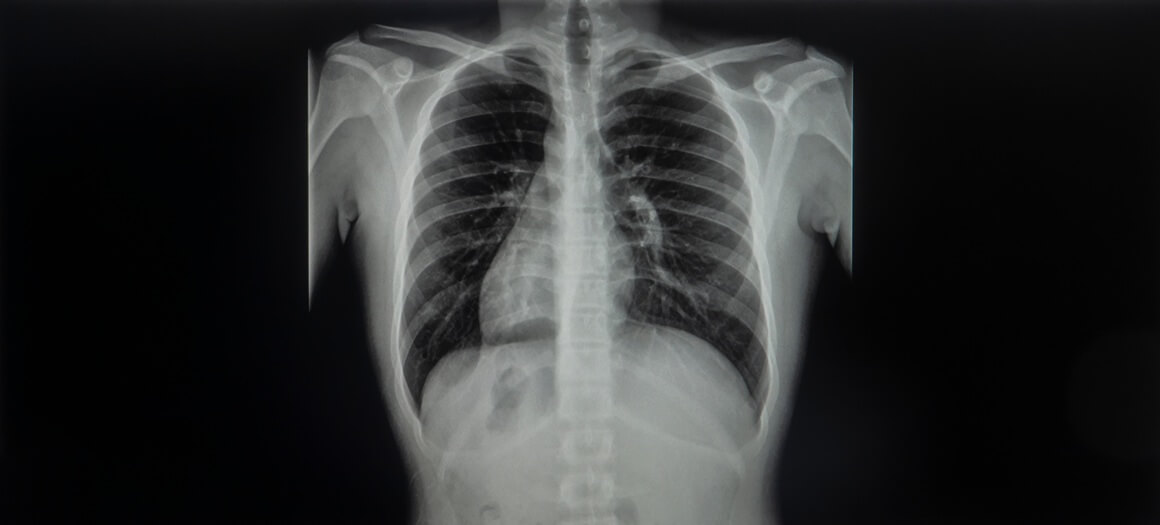

Kod osoba s dekstrokardijom srce se nalazi na desnoj strani prsnog koša, umjesto na lijevoj. Kada je dekstrokardija udružena sa situs inversusom, i drugi organi – poput pluća, jetre, želuca i slezene – također su “zrcalno” raspoređeni.

Pojam “situs inversus” označava upravo takav obrnuti raspored unutarnjih organa, a ako su svi glavni organi smješteni na suprotnim stranama, stanje se naziva situs inversus totalis.

Kao i u slučaju Catherine O’Hara, mnoge osobe nikad ne posumnjaju da imaju ovo stanje. Dijagnoza se često otkriva slučajno, primjerice tijekom rendgenskog snimanja prsnog koša, elektrokardiograma (EKG-a) ili ultrazvuka srca koji se rade iz nekog drugog razloga.

Budući da je srce smješteno na suprotnoj strani, nalazi poput EKG-a mogu izgledati neuobičajeno ako liječnici unaprijed ne znaju za postojanje dekstrokardije. Ako nema simptoma i nema potrebe za snimanjem, neki ljudi nikad ni ne saznaju da imaju ovo stanje.